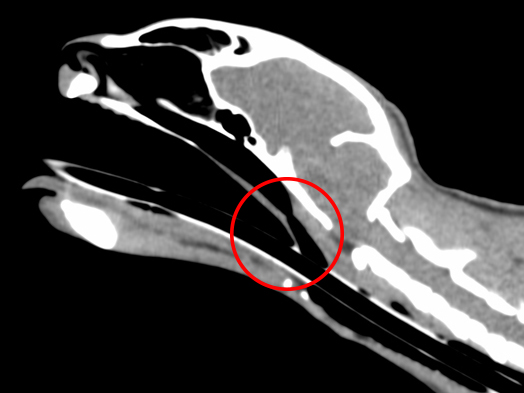

CT検査:赤丸が狭窄部位